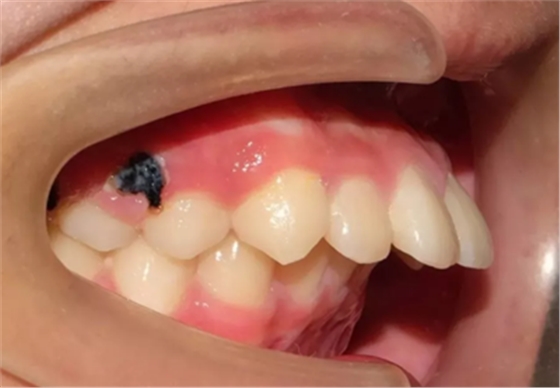

04 開合

因經(jīng)常吃不了瓜子,口腔不能執(zhí)行撕咬的動作或食物咬不斷前來就診,該如何避免?